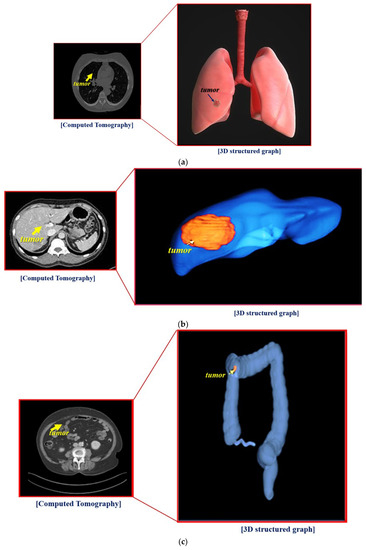

An HDMI cable connects the hologram with the laptop, and Wi-Fi connection is also available. However, for security reasons, a wired connection is recommended. In addition, the notebook is connected to a Picture Archiving and Communication System (PACS) server and can provide computed tomography (CT) or magnetic resonance imaging (MRI) images of tissues (for example, lungs, liver, colon, stomach, and brain) as shown in Figure 6. Video can be shown both in Windows and Linux environments. However, for general use, the window preferences may be appropriate. The overall picture of the holographic system was taken during the hologram experiment.

The overall size of the hologram system is 6.15 × 26.0 × 39.0 cm3, and the fabricated hologram system is shown in Figure 9. The imaging files of the lungs, liver, and colon can be obtained using the collection of medical servers with PACS tools thought the department of radiology by Gachon University Gil Medical Center in Korea.

As shown in Figure 9, the images of the lungs, liver, and colon are used for a CT program. Thus, the CT images of organs can be sent to the laptop and transmitted to the hologram system.

Figure 6. Test results obtained using the proposed hologram system: (a) Lung, (b) Liver, and (c) Colon.